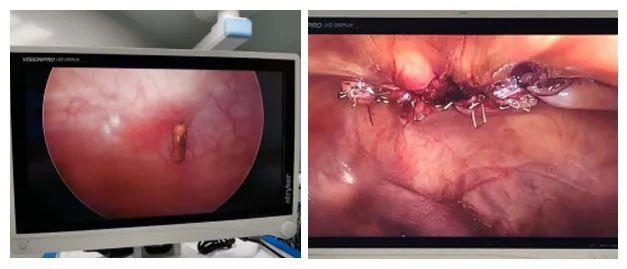

膀胱镜下可见右侧输尿管上方6cm膀胱壁可见一大小约1.0*0.5cm的异物,嵌顿于膀胱壁。精准定位后行腹腔镜手术治疗,采用超声刀充分分解粘连,沿异物边界完全游离,使用腔镜下一次性切割闭合器,离断并夹闭膀胱后壁,术程顺利。

术中无损伤,证实异物为节育器。将标本取出,未见出血,留置潘氏管1根。术后行补液等对症治疗,无漏尿,术后3天拔除引流管,患者痊愈出院。